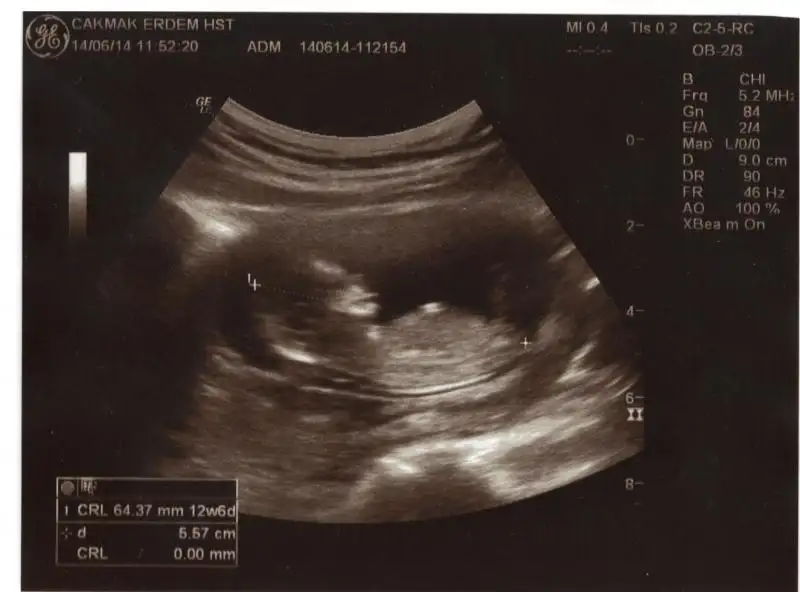

dr soylemeden siz gorun genital nub teorisi ( bebegin cinsiyeti)

Masallah cnm erkek bnce çikintı dik bide bas popo uzunluk oranı erkek fikrine kapılmma ndn oldu

evt bu resim icin erkek dedim cnm bnmm yukari bakio nub ucu